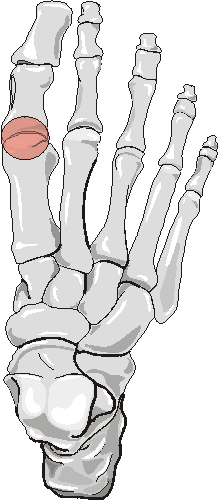

Silastic Hemiarthroplasty with large erosions 1st MT head, status post fusion 1st IP jointSILASTIC ARTHROPATHY is due to foreign body reaction to silicone particles.

In the foot, the 1st metatarsophalangeal joint is the joint most commonly involved, as it is the joint most commonly replaced.

2. Erosion pattern: The most common finding is the presence of erosion and osteolysis of bone adjacent to the implant.